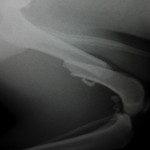

【症例紹介】大腿骨骨折

大腿骨骨折とは

大腿骨とは骨盤とすねの骨の間にある太ももの骨です。

落下、事故などでおれてしまいます・・・

1例は2骨片の骨折です。